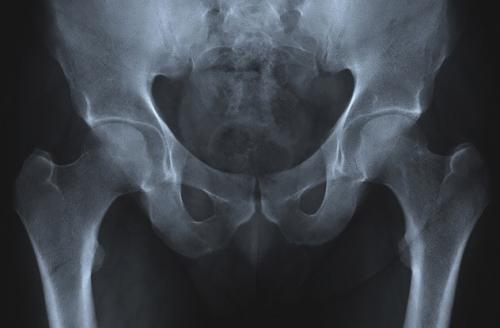

9. Суперплотные кости

С возрастом появляется проблема остеопороза, то есть потеря костной массы и её плотности. Это приводит к неизбежным переломам, деформациям и разрушению. Тем не менее, существует группа людей с уникальным геном, который может стать ключом к лечению остеопороза. Ген найден у южноафриканцев с голландским происхождением (африканеров). Это мутации в гене SOST, который контролирует белок (склеростин), регулирующий рост костей. Сейчас исследователи изучают ДНК африканеров в надежде найти способы, чтобы обратить вспять остеопороз и другие возрастные скелетные деформации.